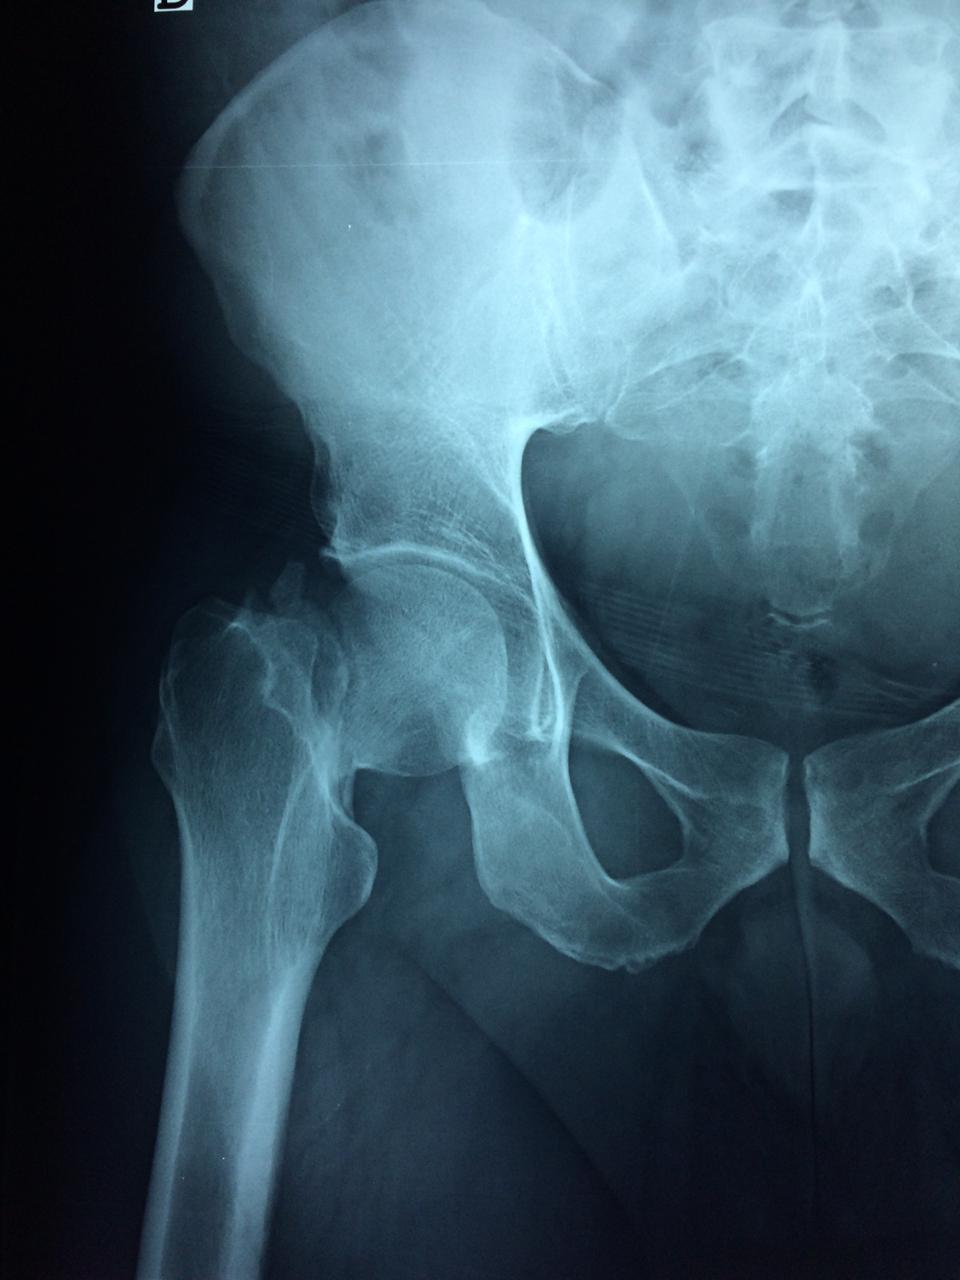

La cirugía de fractura de cadera se realiza para reparar una ruptura en la parte superior del hueso del muslo. Este hueso se denomina fémur.

Es parte de la articulación coxofemoral. Si una fractura de cadera no recibe tratamiento, es posible que deba permanecer en una silla o en la cama.

A menudo se recomienda la cirugía para reparar la fractura debido a dichos riesgos.